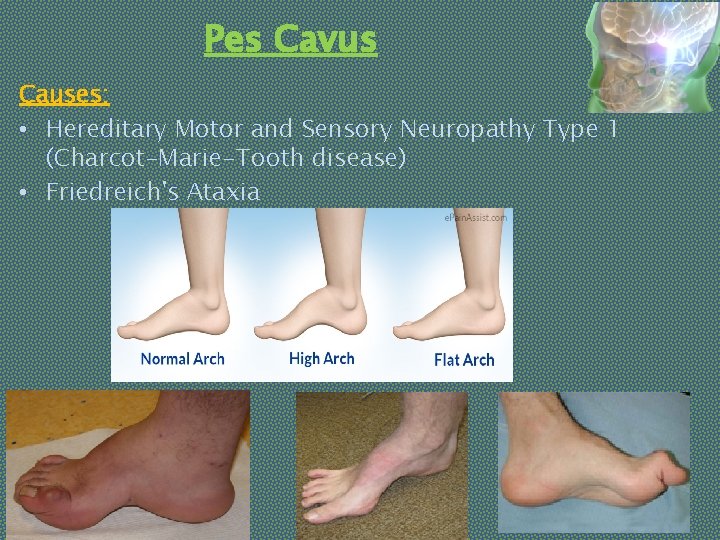

Friedreich’s Ataxia Ø Sensory Ataxia, Romberg’s sign may be +ve Ø Cerebellar Signs (nystagmus, scanning speech, intension tremors) may be present Ø Associated features: § Pes cavus (high arched foot) § Kyphoscoliosis § Spina Bifida § Hypertrophic Obstructive Cardiomuopathy (HOCM)

Pes Cavus Causes: • Hereditary Motor and Sensory Neuropathy Type 1 (Charcot-Marie-Tooth disease) • Friedreich's Ataxia